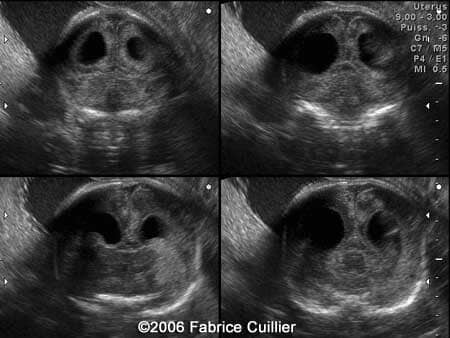

A 30-year-old woman, gravida 2, para 1, was referred  to our institution at 28 weeks to perfom an anomally scan. The following brain images were obtained:

An ultrasound examination was performed in our unit at 30 weeks to evaluate the fetal anatomy. An abdominal scan demonstrated a bilateral hydrocephaly associated with echogenic signs on the brain suggestive of calcifications.

An additional endovaginal scan was performed. There were one large cyst on the right hemisphere and multiple peripheral cysts. The corpus callosum artery was identified. Fetal biometry was in concordance with the gestational age. Karyotyping was offered (46XX). A PCR was performed in the amniotic fluid sample. The result was positive for the Toxoplasma gondii DNA.

Serial coronal ultrasound view at 30 weeks showing bilateral ventriculomegaly